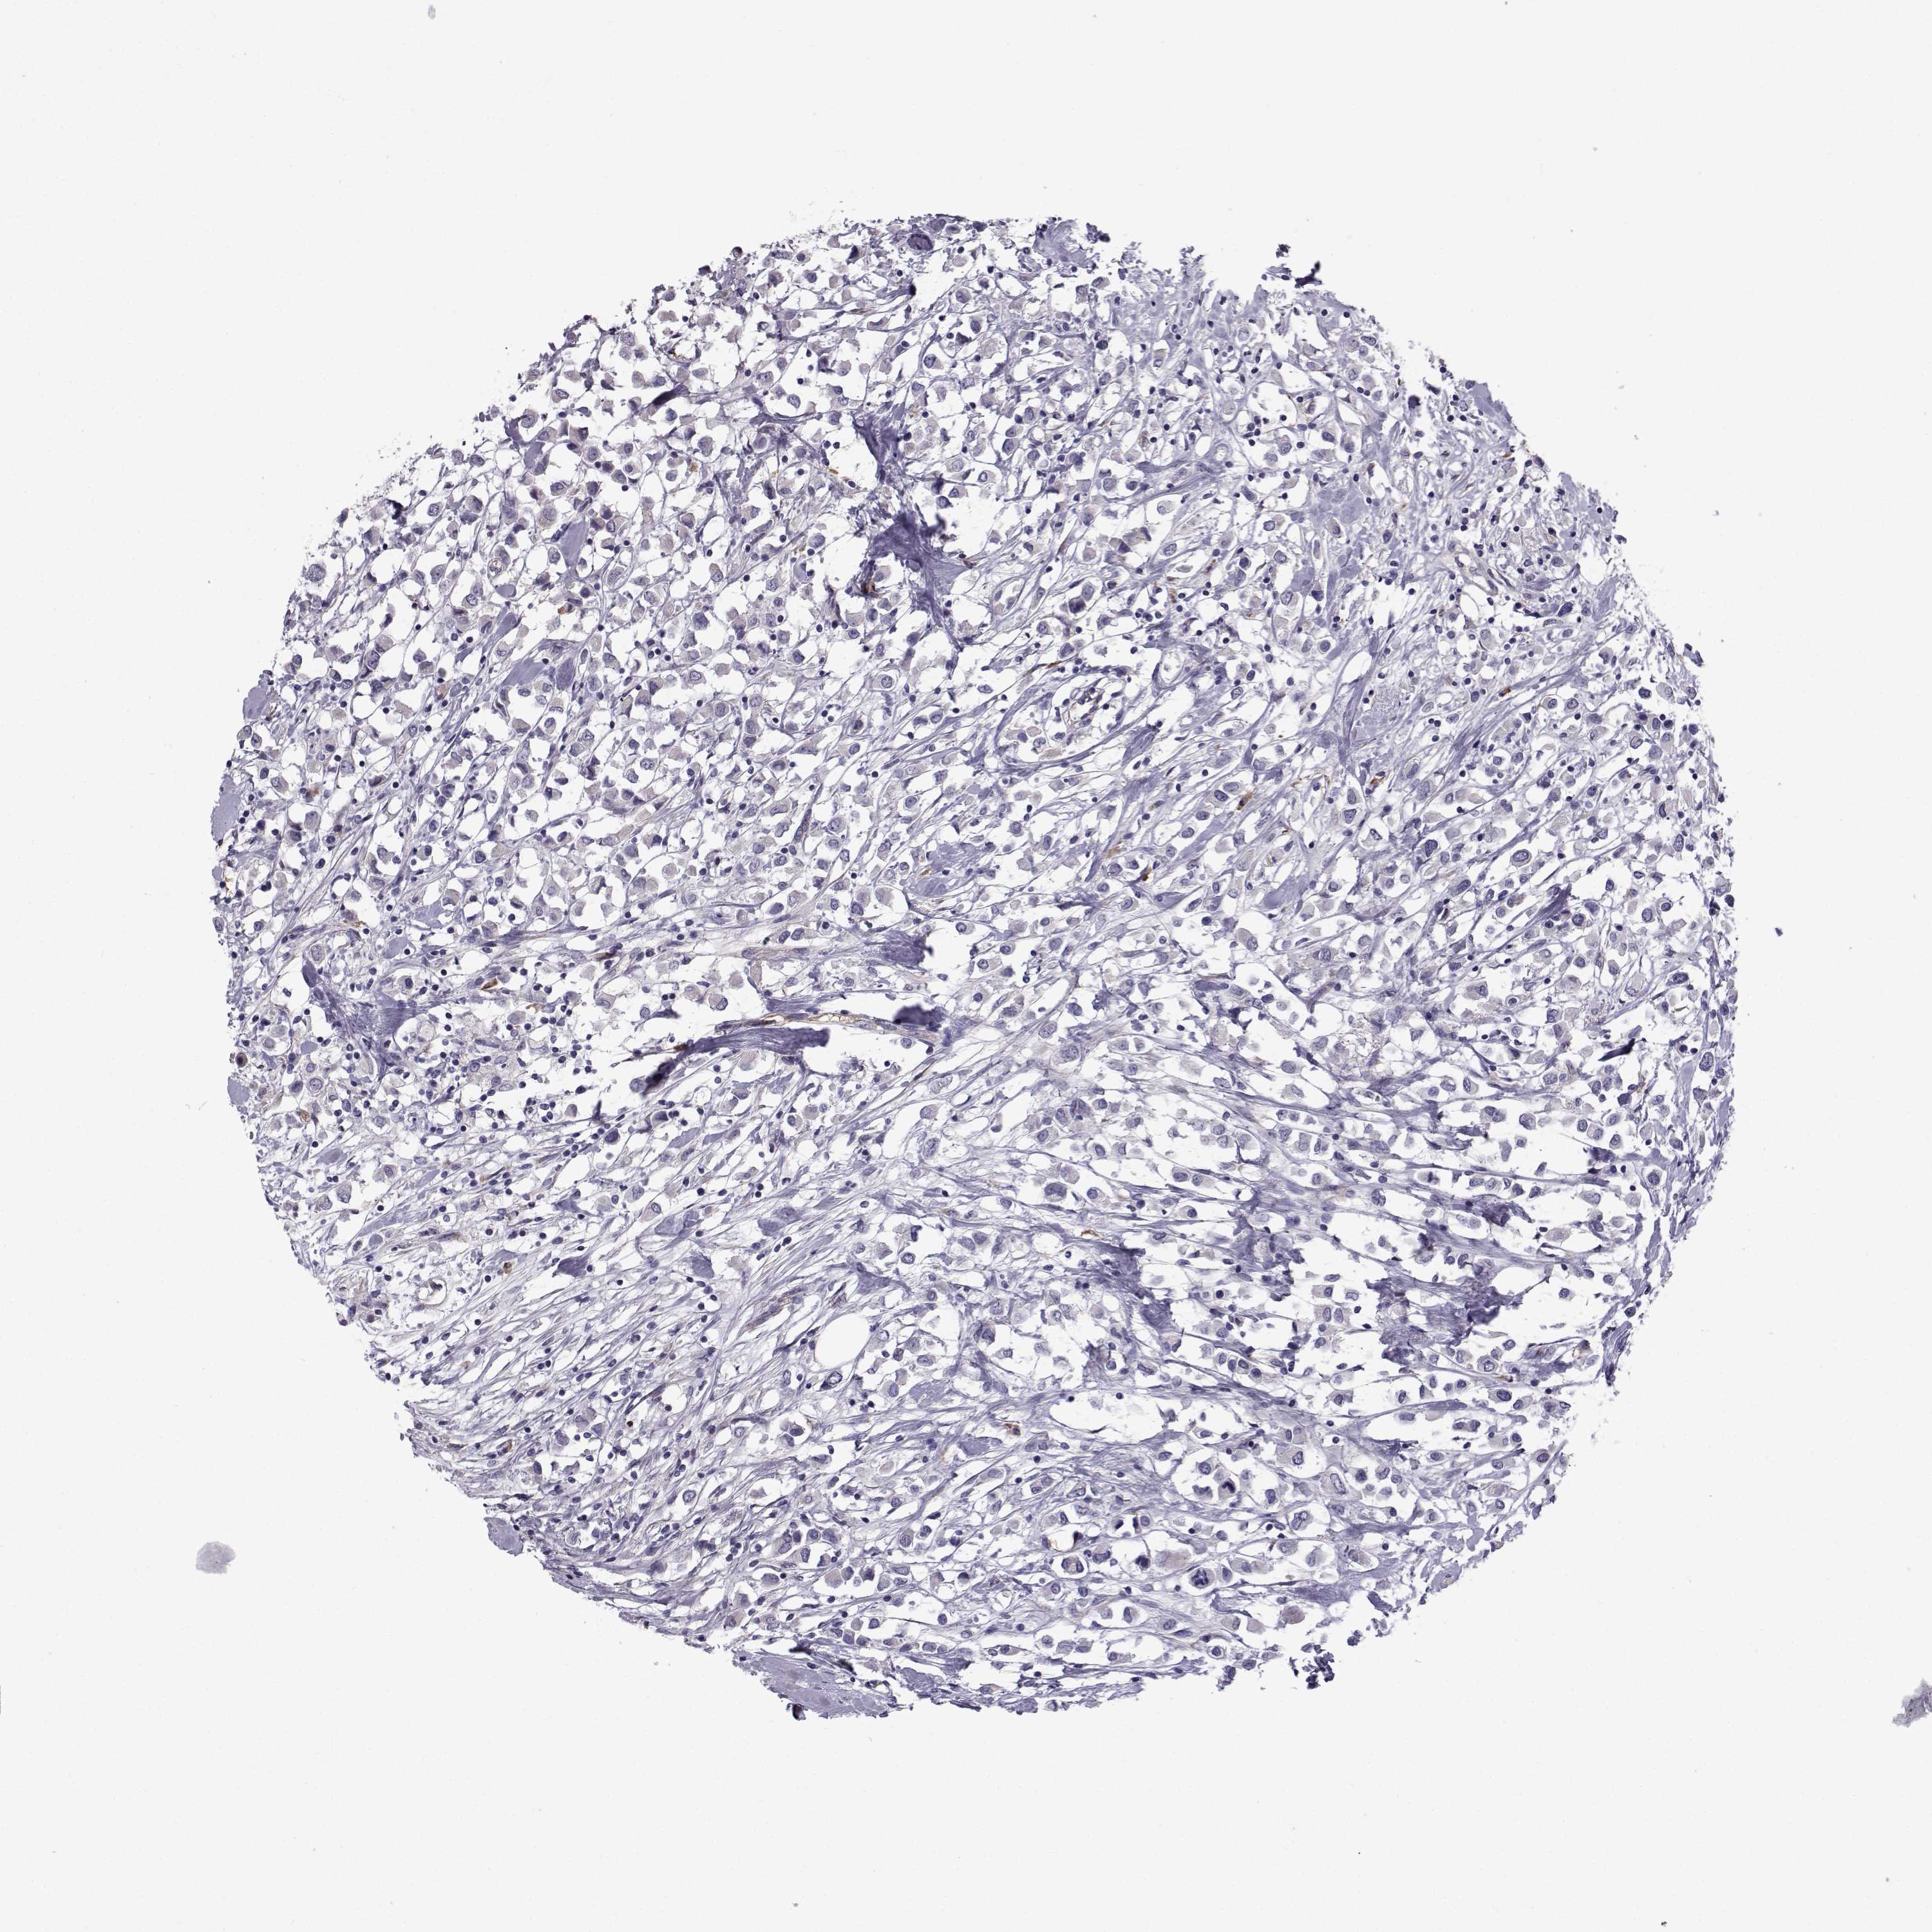

CANCER BREAST CANCER Show tissue menu

Breast cancer

Human cancer